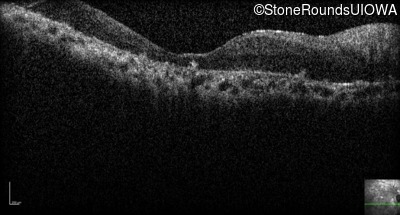

Optical Coherence Tomography - Left - Light Perception

Exemplar